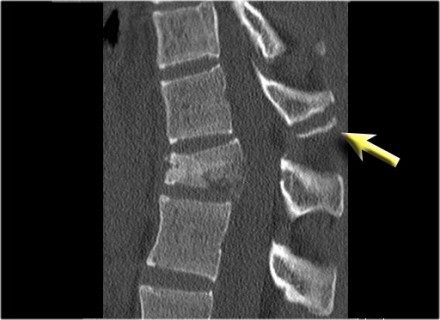

The findings are:

- The main feature is posterior distraction with horizontal fractures of posterior elements (red arrow)

- Avulsion of a spinous process (yellow arrow)

- Widening of facet joint (green arrow)

- Burst-type fracture

In this case some would call this a burst fracture with PLC-injury i.e. 2+3 points.

However the distraction is the most important finding, i.e. distraction and PLC injury, i.e. 4+3 points.